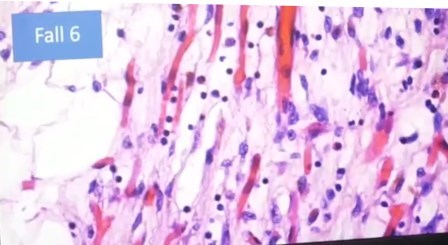

Linfocitos en endotelio, endotelitis

Foco de infección, inflamación no sólo de los vasos sanguíneos, sino múltiple.

Ampliación

«Esto no es autolisis y lo vemos una y otra vez, con desprendimiento del endotelio de los vasos, entotelitis», exclama el científico. Terrible.

«Antes no lo había visto, y yo he visto mas de 40 mil autopsias y 500 mil biopsias, estas células que se han desprendido no es autolisis, porque hay también eritrocitos, que son las células largas, y no pueden estar allí después de la autolisis y lo vemos una y otra vez. Hay desprendimiento de células endotélicas», detalla.